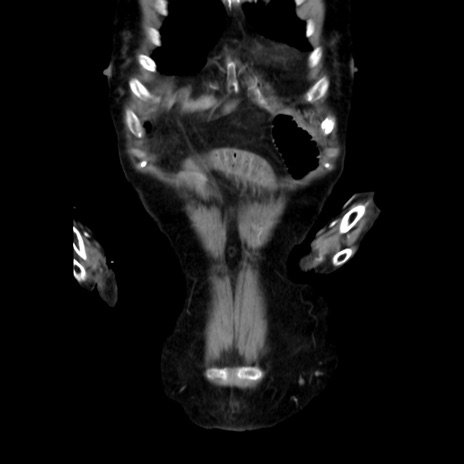

症例40(冠状断像)

冠状断像